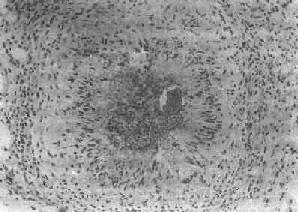

图19-6 血吸虫病之晚期急性虫卵结节 坏死区及嗜酸性粒细胞浸润范围缩小,其周围出现放射状排列的类上皮细胞层 (2)慢性虫卵结节:急性虫卵结节经10余天后,虫卵内毛蚴死亡,坏死物质逐渐被吸收,虫卵破裂或钙化,其周围除类上皮细胞外,出现异物巨细胞和淋巴细胞,形态上似结核结节,故称为假结核结节(图19-7)。少数虫卵结节一开始即为假结核结节,而不经过急性虫卵结节阶段。最后,假结核结节中的类上皮细胞为纤维母细胞代替,并产生胶原纤维,使结节纤维化。其中央的卵壳碎片及钙化的死卵可长期存留。